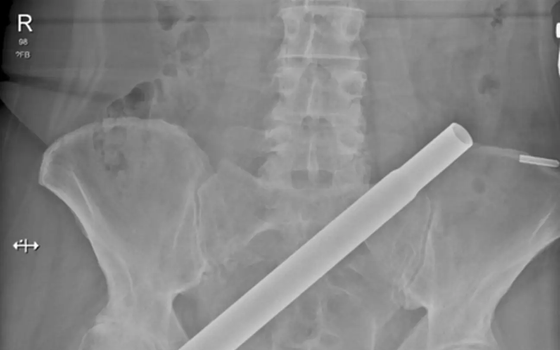

Clinical Case ReportsAs explained by Daisy Hill Hospital medical staff examining the unusual case in Clinical Case Reports, the metal base and stem portion of the tree managed to “impale her through her right buttock into her pelvis.”

They go on to explain that “despite the impressive mechanism of injury, there was no immediate life-threatening bleed and the patient was subsequently transferred to the local Major Trauma Centre for expert surgical management but suffered significant delays due to the lack of clear transfer pathways.”

As if the entire situation wasn’t extraordinary enough, the poor lady had to wait for over an hour and a half for firefighters to safely cut away the pole so the woman could be given properly treated and receive an x-ray. The team then went on to used numerous imaging processes to create a 3D reconstruction of the injury.